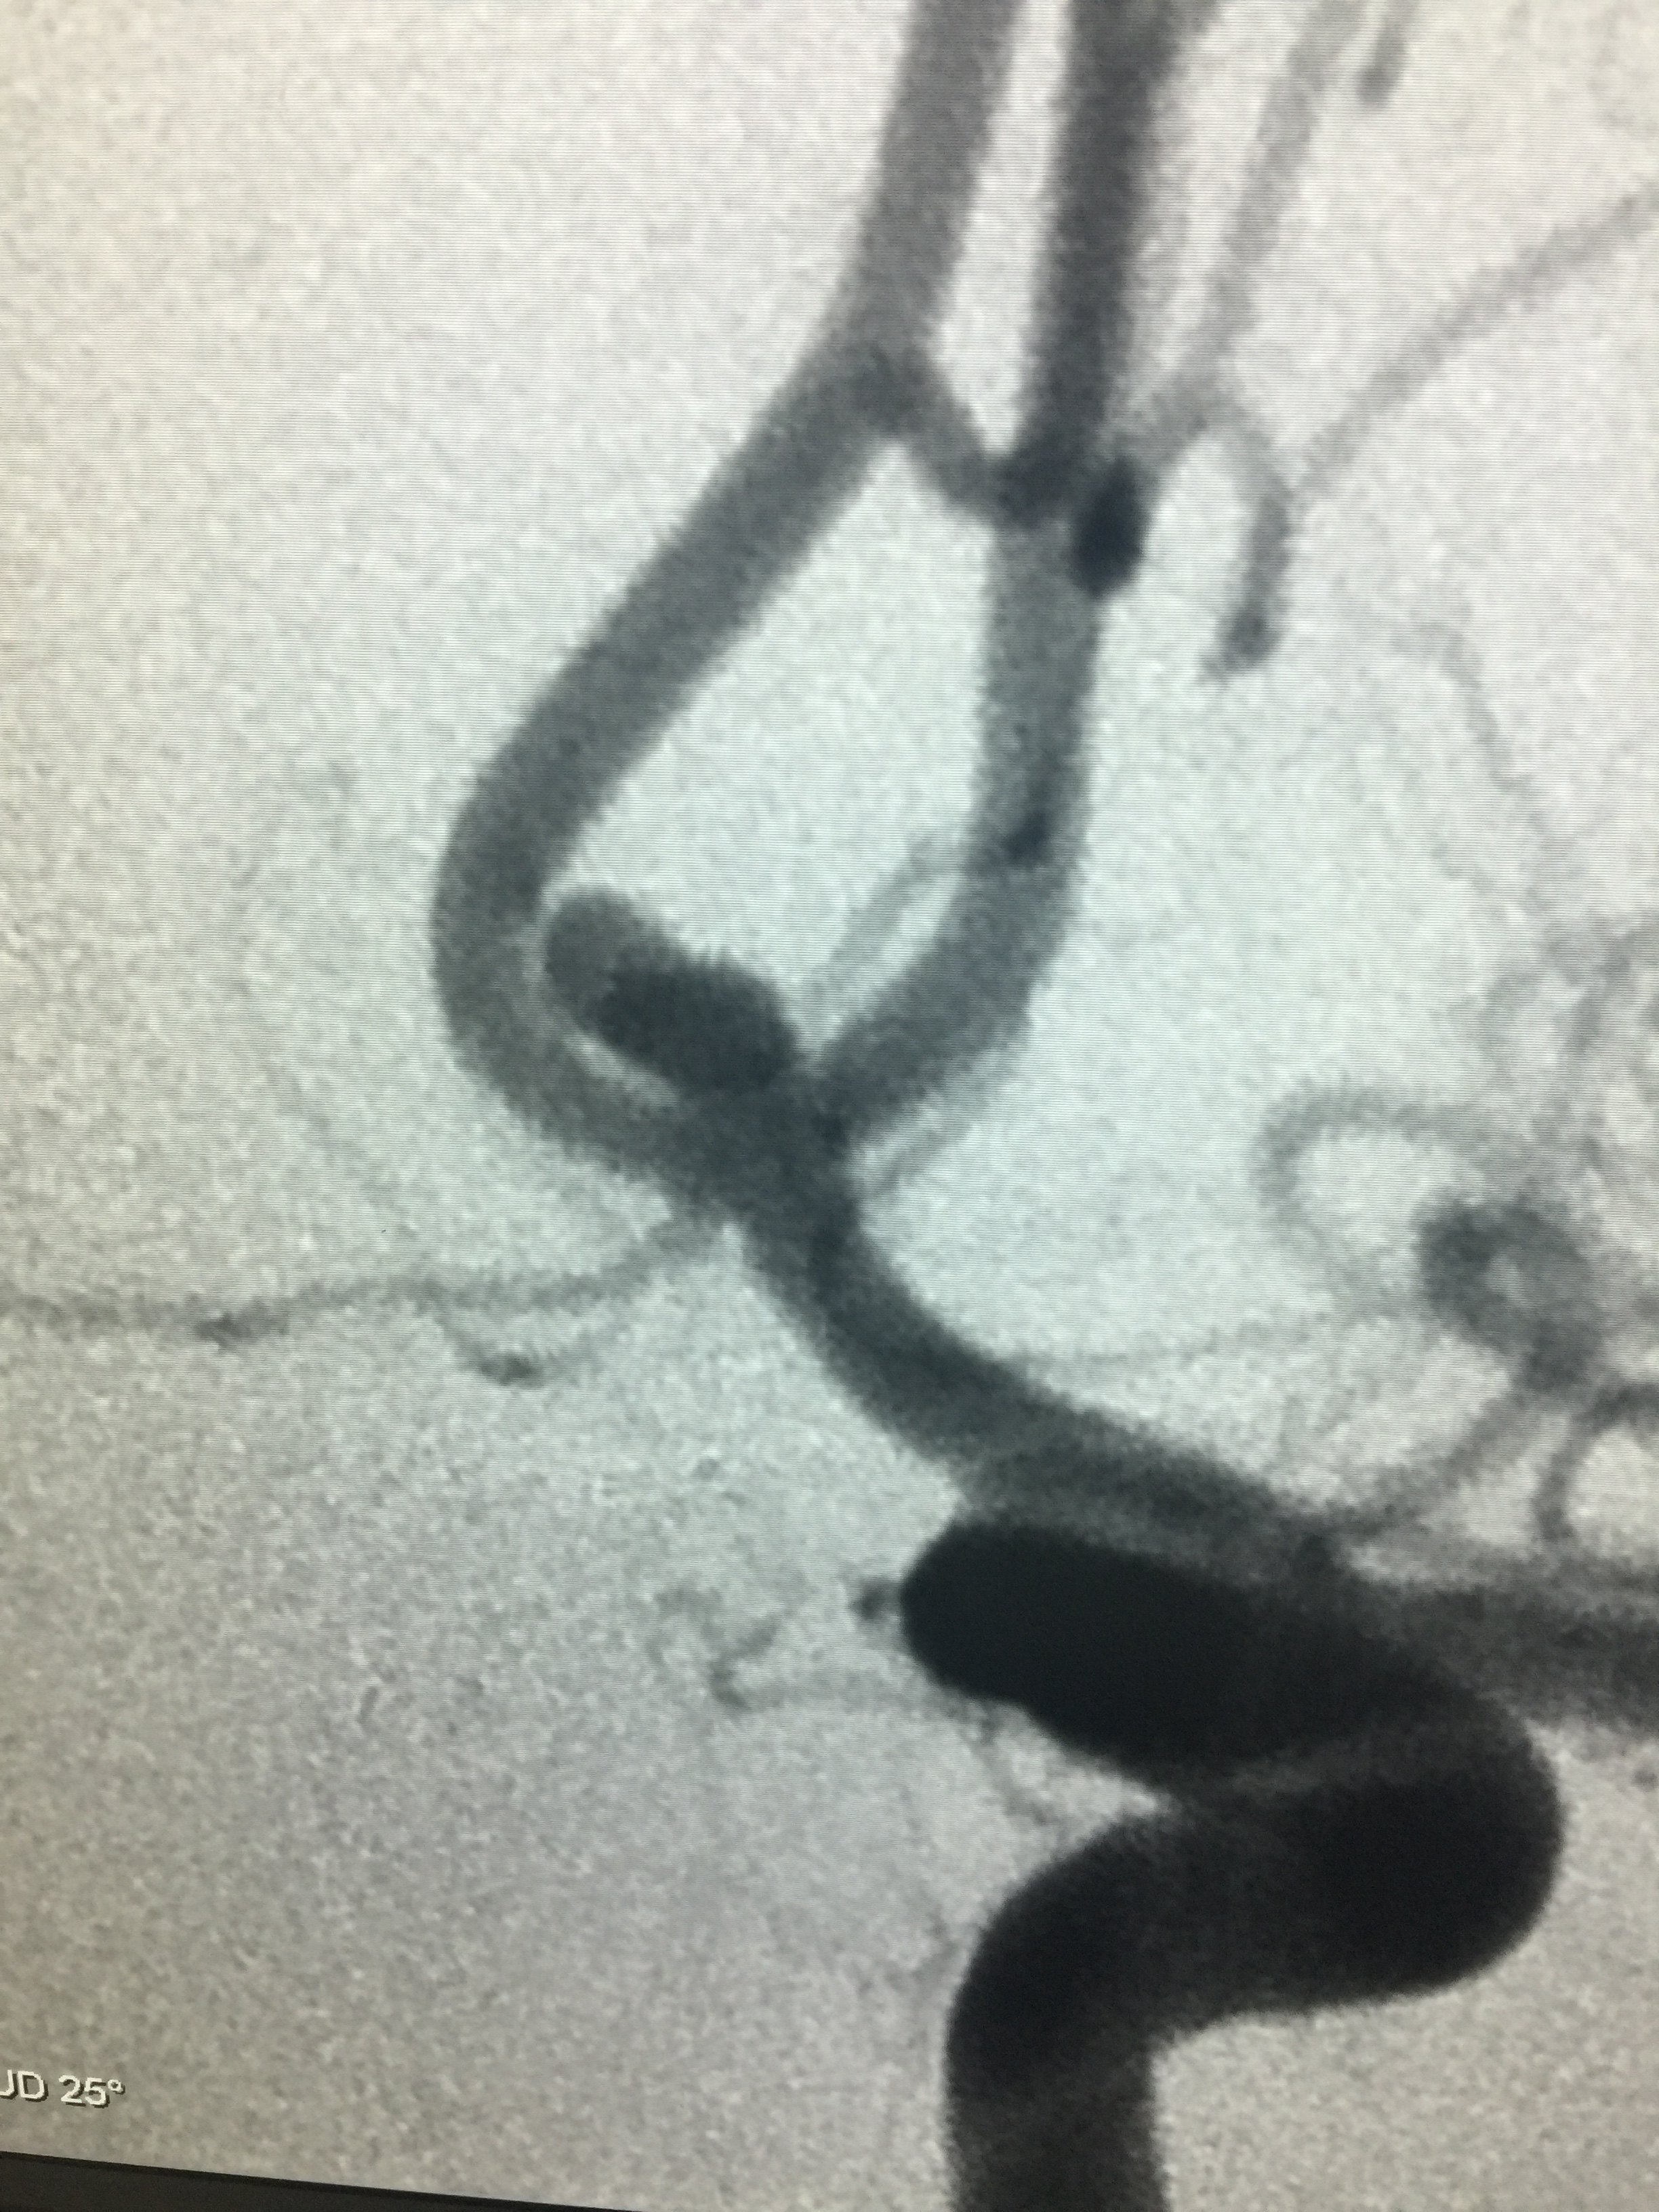

病例一:术前

1534032328.png

术后